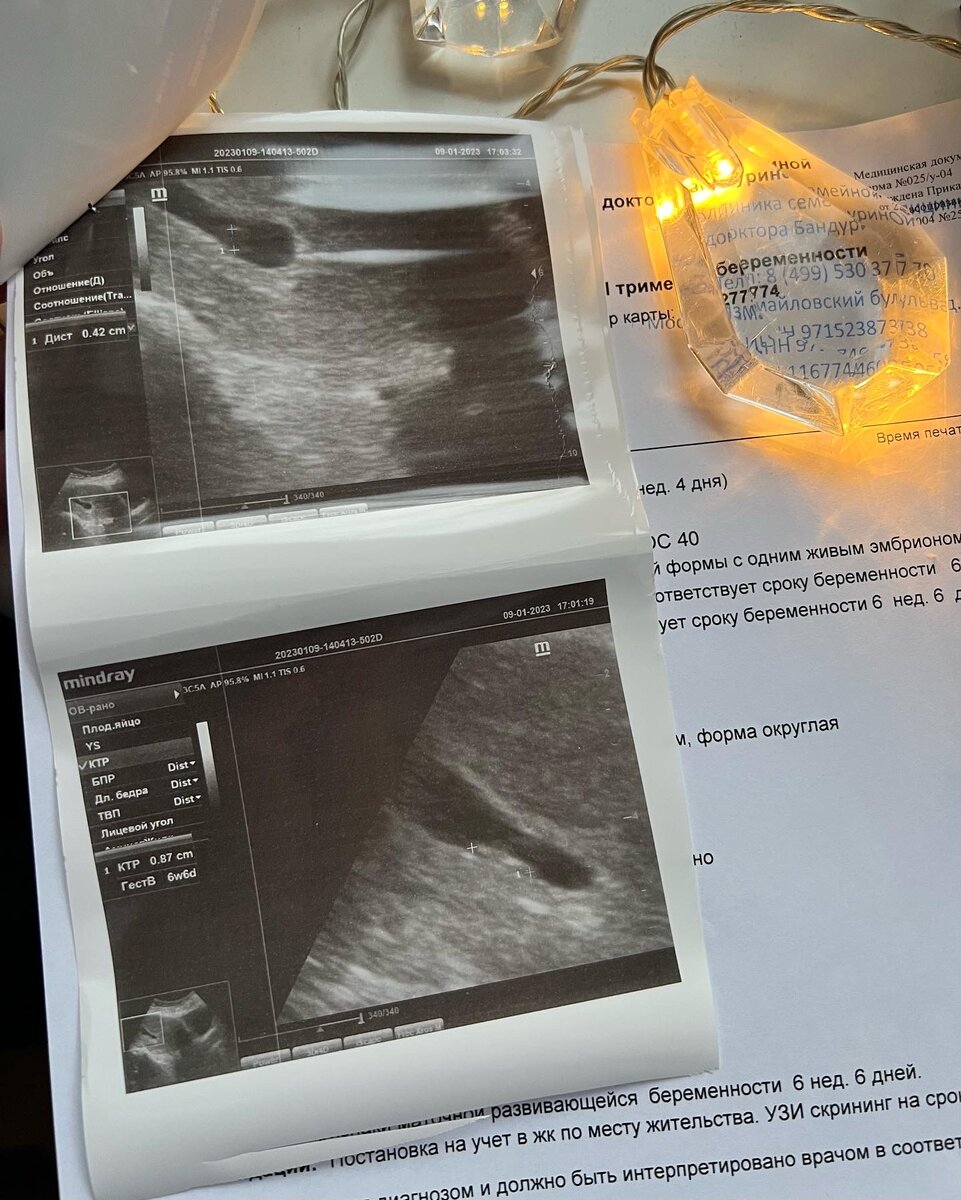

Итак, я беременна, ребеночек на месте, в матке, сердечко бьется! Ура! Пока все в порядке. Я очень счастлива. Все очень счастливы!

Теперь я пишу вам - вот сердечко бьется, я могу вставать на учет в ЖК. Срок 7 недель. Размер эмбриончика 8-9мм.